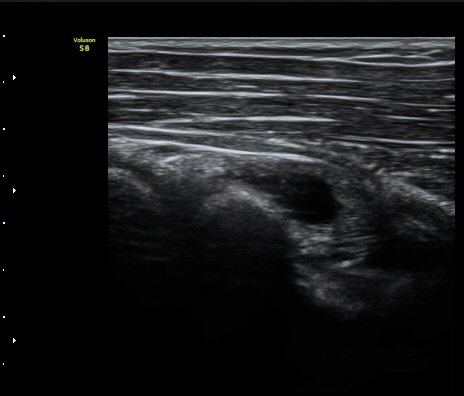

ŽÃËÀÚ¸¦ ¿ä°ñµÎ ºÎÀ§·Î À̵¿ÇÏ´Ï ¿ä°ñµÎ Ç¥Ãþ¿¡ Àú¿¡ÄÚ ³¶Á¾ÀÌ °üÂûµÇ°í ³¶Á¾ÀÇ ¿ÜÃø¿¡¼­

Èİñ°£½Å°æÀÌ ¾Ð¹ÚµÇ°í ÀÖ´Ù(±×¸² 2).

ŽÃËÀÚ¸¦ Á» ´õ ¸»´ÜÀ¸·Î À̵¿ÇÏ´Ï ³¶Á¾Àº ´õ Å©°Ô °üÂûµÈ´Ù(±×¸² 3, 4).